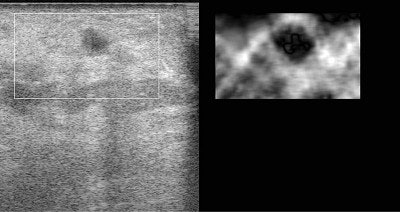

| A phantom with an 8-mm diameter spherical target that is three times stiffer than its background. The target is not visible in the standard B-mode ultrasound image (left), but is obvious in the strain image (right). |